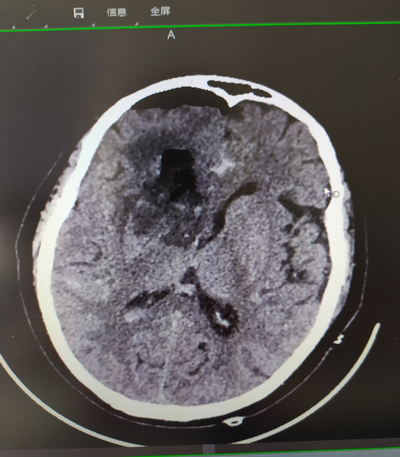

術(shù)后CT顯示

外一科團隊根據(jù)患者具體情況,采取先保守治療,平穩(wěn)降壓,動態(tài)評估再出血風險,待血腫趨于穩(wěn)定后選擇右側(cè)經(jīng)額入路,打開大小約3×3cm小骨窗,選擇相對功能“啞區(qū)”,經(jīng)右側(cè)額中回造瘺,神經(jīng)內(nèi)鏡直視下清除血腫、止血?;颊咝g(shù)后當天早晨恢復正常,目前正在進一步康復中。